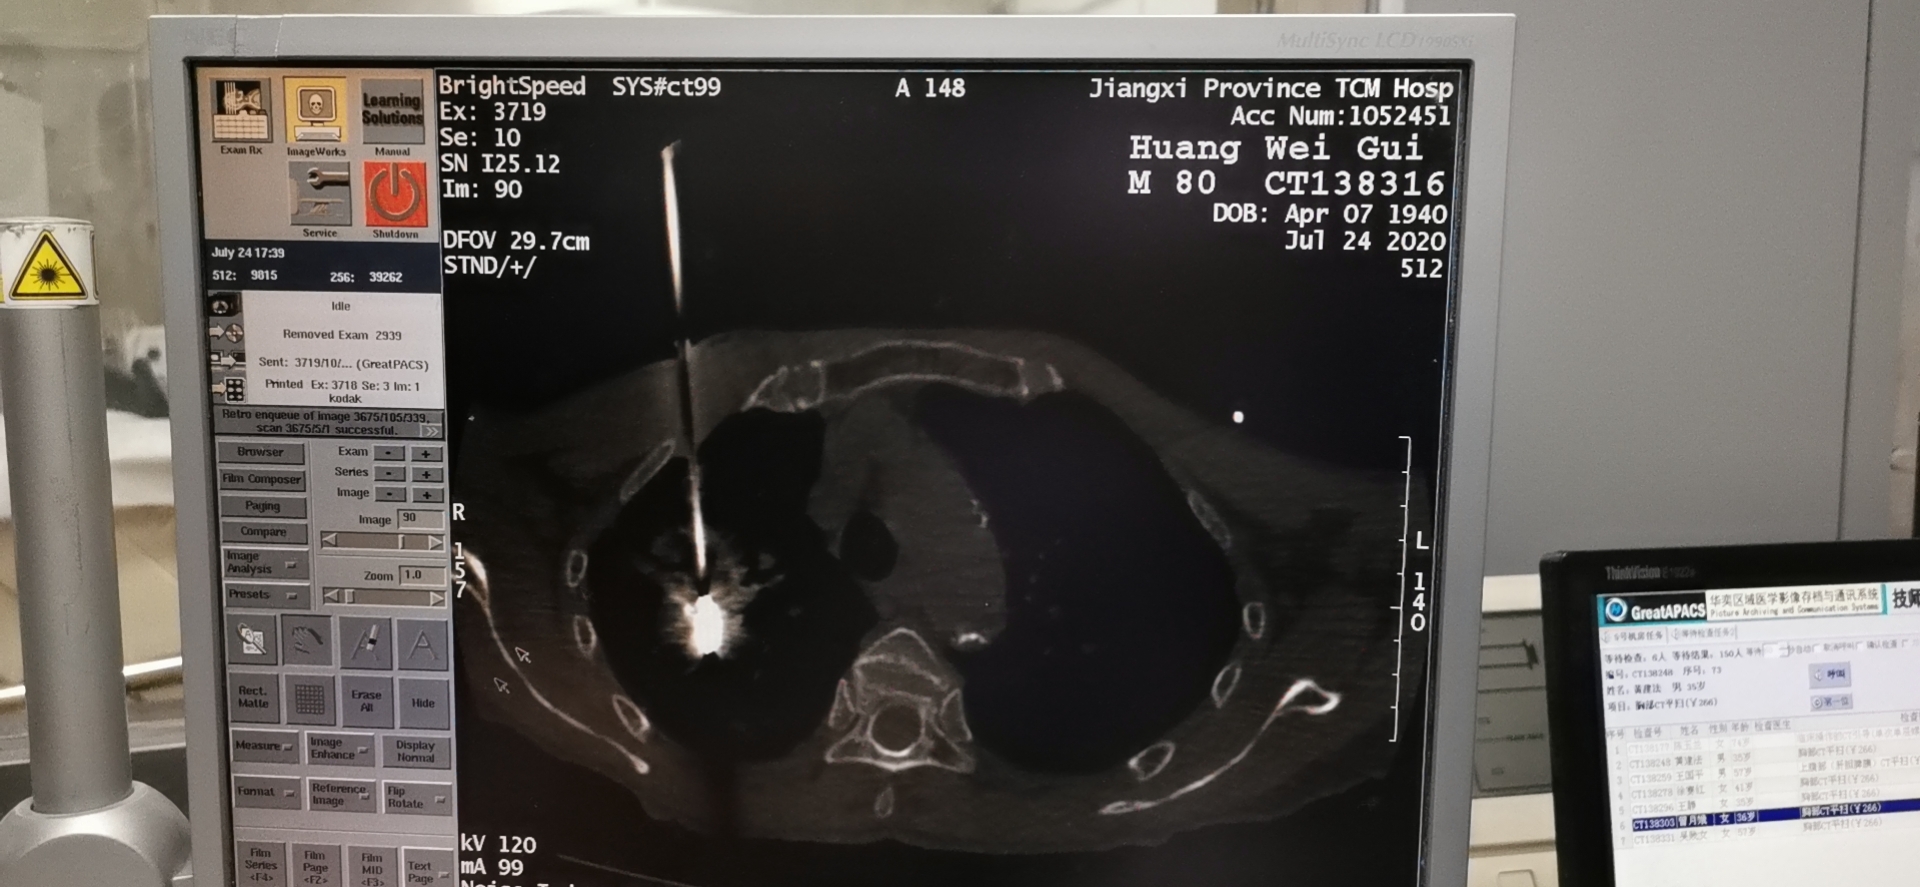

特色优势:1.充分挖掘传统中医药抗癌优势,在辨证口服汤药的基础上,结合穴位贴敷、穴位埋线、火针、刺络拔罐、腹针、耳针、脐疗、中药泡洗、中药熏洗、中药熨烫等各种中医外治技术,辨证食疗等以扶正抗癌。2.紧跟学科发展前沿,依据国内国际最新治疗指南,开展了常见恶性肿瘤的规范化内科治疗,包括化疗、靶向治疗、免疫治疗及临终关怀等治疗。3.开展了各项介入微创技术,包括深静脉穿刺置管术、经外周中心静脉置管术、输液岗、穿刺活检术、微波消融术(热消融术)、康博刀(冷热多模态消融术)、肿瘤血管介入术、腔内支架植入术等。4.身心同调,人文关怀:重视患者及家属生活质量、心理健康。通过举办患教会、患者答疑会、创建肿瘤康复俱乐部、带领患友进行八段锦练习等方式,探索群体抗癌、身心同调的防治模式。